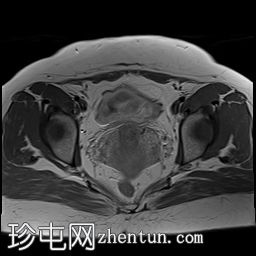

冠状位

T1加权像

可见子宫外腹腔内妊娠囊,内含胎儿组织。

该妊娠囊向后推移子宫,并与剖宫产瘢痕凹陷处紧密相连。

该妊娠囊与相关肠袢无法分离。可见其与性腺血管密不可分,且性腺血管明显突出。

胎盘位于妊娠囊后方,紧贴子宫前壁。

沿妊娠囊下缘可见一处异质性局灶性积液,最大轴向尺寸约为 8.4 × 5.5 cm,T1 加权像呈异质性高信号,T2 加权像呈异质性中等信号,T1 脂肪抑制序列未见信号下降,提示为血液成分。该积液压迫膀胱。

可见周围脂肪间隙呈条索状改变。

左侧卵巢无法辨认。

右侧卵巢未见实性或囊性肿块。

子宫体积增大,后倾,子宫内膜厚度约 1 cm,子宫下段前壁可见局灶性变薄(既往子宫瘢痕)。子宫连接区完整,未见肌层肿块。可见子宫内膜腔边缘有血性分泌物。